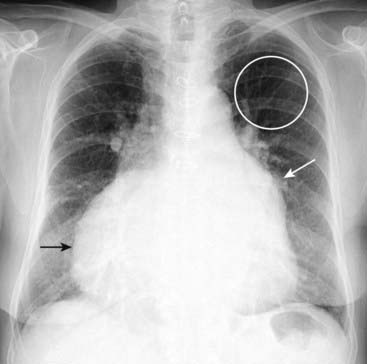

Thoracic Aortic Dissection

image Aortic dissections most often originate in the ascending aorta (Stanford type A) or may involve only the descending aorta (Stanford type B).

image They result from a tear that allows blood to dissect in the wall for varying lengths of the aorta, usually along the media.

image In general, patients with aortic dissection have been hypertensive and may have an underlying condition that can predispose to dissection, such as cystic medial degeneration, atherosclerosis, Marfan syndrome, Ehlers-Danlos syndrome, trauma, syphilis, or crack cocaine abuse.

image In many patients, abrupt onset of ripping or tearing chest pain, which is maximal at its time of origin, is the characteristic history.

image Conventional radiographs are not significantly sensitive to be diagnostically reliable, but they may point to the diagnosis when several imaging findings occur together, especially in the proper clinical setting.

“Widening of the mediastinum” is a poor means of establishing the diagnosis because it is commonly overinterpreted on portable supine radiographs while, on the other hand, it occurs in only about 1 in 4 cases of aortic dissection.

Left pleural effusion (which frequently represents a transudate caused by pleural irritation, although transient hemorrhage from the aorta can also produce a hemothorax) (Fig. 9-27).

image

Figure 9-27 Aortic dissection.

Conventional radiographs are not sensitive enough to be diagnostically reliable for aortic dissection, but they may point to the diagnosis when several imaging findings are seen together, especially in the proper clinical setting. “Widening of the mediastinum” is frequently not present and is a poor means of establishing the diagnosis, although in this patient the mediastinum is clearly widened by an enlarged aorta (double black arrow). Also, a left pleural effusion is present (solid black arrow). The combination of a widened mediastinum and a left pleural effusion in a patient with chest pain should alert you to the possibility of an aortic dissection.

imageOn both MRI and CT, the diagnosis rests on identification of the intimal flap that separates the true (original) from the false lumen (canal created by the dissection) (Fig. 9-28).

image In general, type A (ascending aortic) dissections are treated surgically, whereas type B (descending aortic dissections) are treated medically.

Figure 9-28 Aortic dissections, types A and B.

A, An intimal flap is seen to traverse both the ascending (solid black arrow) and descending aorta (dotted black arrow). This is a Stanford type A dissection. B, There is a normal-appearing ascending aorta (dotted white arrow) while an intimal flap is noted by the black line traversing the descending aorta (solid black arrow). The intimal flap is the characteristic lesion of an aortic dissection. The smaller lumen is usually the true (original) lumen, and the larger, false lumen is actually a channel that has been produced by blood dissecting through the media.